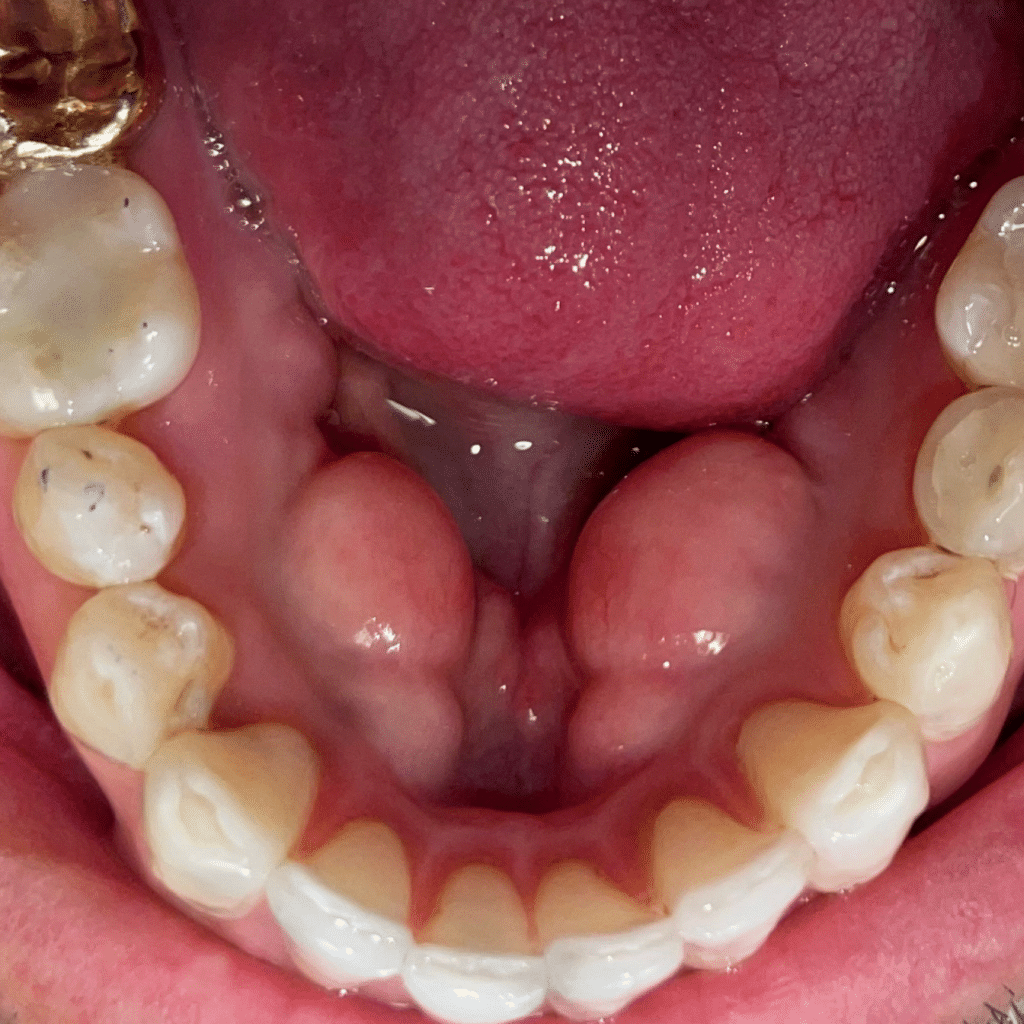

A perfect smile revealinvolving pulpotomies / stainless steel crowns

Before

Look how happy our patient looks after she received the services here at South Airdrie Smiles. We did buildups on her teeth and then recently provided pulpotomies / stainless steel crowns for the two teeth we built up. Her teeth were severely worn down. Now, she can’t seem to get enough of her gorgeous smile!